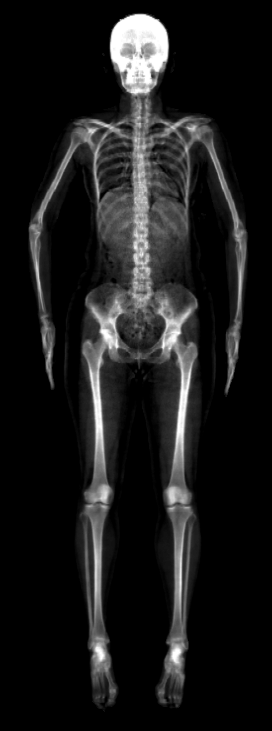

The key problem, however, is obtaining training data that simultaneously gives the inside and outside of the body in 3D. Most imaging technologies that simultaneously capture the inside and outside of the body use ionizing radiation, which is harmful to humans; e.g. Computed Tomography (CT) and X-rays. This means that such data is extremely limited, preventing learning-based methods. Our insight is to use dual-energy X-ray absorptiometry (DXA) data. DXA scans use low-dose X-rays to measure bone mineral density and body fat composition. The radiation level is so low that it is certified to be used on healthy patients for clinical studies, such as the UK Biobank [36]. In a DXA scan, two images are computed by combining two different energy levels: a soft-tissue image and a bone image (Fig. 2). In the silhouette of the body can clearly be seen, whereas reveals the structure and shape of the bones.

From the input images (, ), we compute the corresponding skin and skeleton segmentation masks (, ). For the skin mask , we threshold . As some small artifacts remain, mainly due to pixels in the lungs with low intensity values, we detect the closed contours on the image and fill in small areas. In Fig. 2 we show pairs of input and the obtained mask .